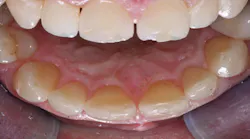

The patient requested an esthetic improvement of his anterior region. He was not happy with the position of his central incisors. After an old orthodontic treatment, a misalignment had developed and needed to be corrected using minimally invasive methods (figure 1).

After examining the position, shade, and stability of the hard and soft tissues, we decided to treat the case with a nonprep veneer made from lithium disilicate for tooth 9. For the restoration material, we chose IPS e.max Press HT (Ivoclar) because of its impressive esthetic properties (figure 2). The veneer was produced by dental technician Roberto Della Neve in Naples, Italy.